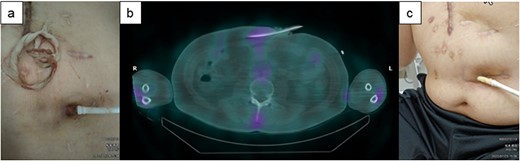

A 49-y-old woman with hypertrophic cardiomyopathy underwent LVAD implantation (HeartMate II™, Abbott Co., Abbott Park, IL, USA) and was readmitted to our institution for DLI 4.5 y after this implantation. Skin induration, tenderness along the driveline tunnel, and bleeding and purulent discharge from the driveline tunnel space were found; furthermore, the culture from driveline drainage showed Pseudomonas aeruginosa (Fig. 5a). Although surgical relocation of the DLES was considered, 67Ga SPECT showed a high signal up to 5 cm inside the DLES (Fig. 5b), and the range of cutaneous infection was limited to 5 cm from the site. Therefore, the catheter cleaning method paired with intravenous antibiotics was selected. Consequently, the exuded solution became clear, and the amount gradually decreased. The patient’s DLI gradually improved (Fig. 5c), and she was discharged from our hospital on day 57 after hospitalization.

The clinical course of development of the DLI in Case 3. (a) Skin induration and tenderness along the driveline tunnel and bleeding and purulent discharge from the driveline tunnel space were found. (b) 67Ga SPECT suggested a high signal up to 5 cm inside the DLES. (c) The exuded solution became clear, and the amount gradually decreased. The patient’s DLI gradually improved.